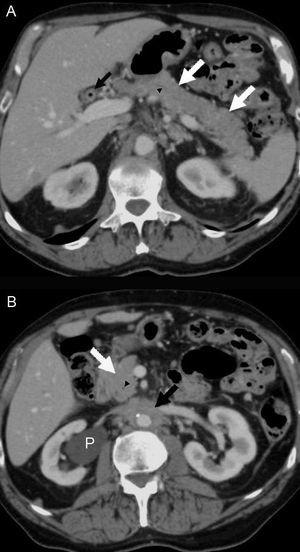

Diecinueve meses después de la cirugía, el paciente refirió un dolor lumbar de carácter sordo, edema bilateral de extremidades inferiores (+++), hidrocele bilateral y edema del pene. La ecotomografía abdominal mostró hidronefrosis derecha y una tomografía computarida de abdomen, un tejido periaórtico que comenzaba en la arteria mesentérica superior y envolvía a la aorta y a la vena cava inferior, extendiéndose hasta la bifurcación aórtica. Existían pequeñas adenopatías retroperitoneales. Los uréteres estaban libres hasta la vejiga. La imagen era indicativa de fibrosis retroperitoneal. El páncreas era radiológicamente normal (figura 1 y figura 2). Los exámenes de laboratorio mostraron anemia (Hto 35,2%, Hb 11,2 g/dl), VHS 50 mm/hora y creatinina 1,2 mg/dl. El recuento de glóbulos blancos fue 5.600 mm3, plaquetas 168.000 mm3, sedimento urinario normal, proteinuria 202 mg/24 horas, proteinemia 7,4 g/dl, albúmina 4,4 g/dl, globulinas 3,0 g/dl, uricemia 5,8 mg/dl, TSH 3,2 µU/l y APE 0,27 ng/ml. Con el diagnóstico clínico de fibrosis retroperitoneal idiopática se inició tratamiento con corticoides (deflazacort) 30 mg/día, colchicina 0,5 mg cada 12 horas y omeprazol 20 mg/día. Se eligió el deflazacort (DEF) por el antecedente de osteoporosis, dado su menor efecto sobre el metabolismo óseo. Un mes después el paciente estaba asintomático. Habían desaparecido el dolor lumbar, la anemia y el edema genital y de las extremidades inferiores. La VHS y la PCR se habían normalizado (8 mm/hora, <1 mg/l, respectivamente) y la función renal era normal. Se redujo el DEF a 22,5 mg/día, manteniendo la colchicina en 1 mg/día, enalapril, omeprazol, calcio y vitamina D. A los 2 meses de terapia se quejó de un leve dolor lumbosacro, había una discreta elevación de la VHS (18 mm/h) y de PCR (3,3 mg/l), por lo cual se aumentó el DEF a 30 mg/día. Al tercer mes estaba asintomático y la VHS y PCR se habían normalizado. Una tomografía computarida mostró una reducción del volumen del tejido retroperitoneal en un 25% (figura 2). Se redujo el DEF a 22,5 mg/dl manteniendo sin modificación los demás fármacos.

Figura 1. Tomografía computarizada con contraste intravenoso relaizada en julio de 2008.